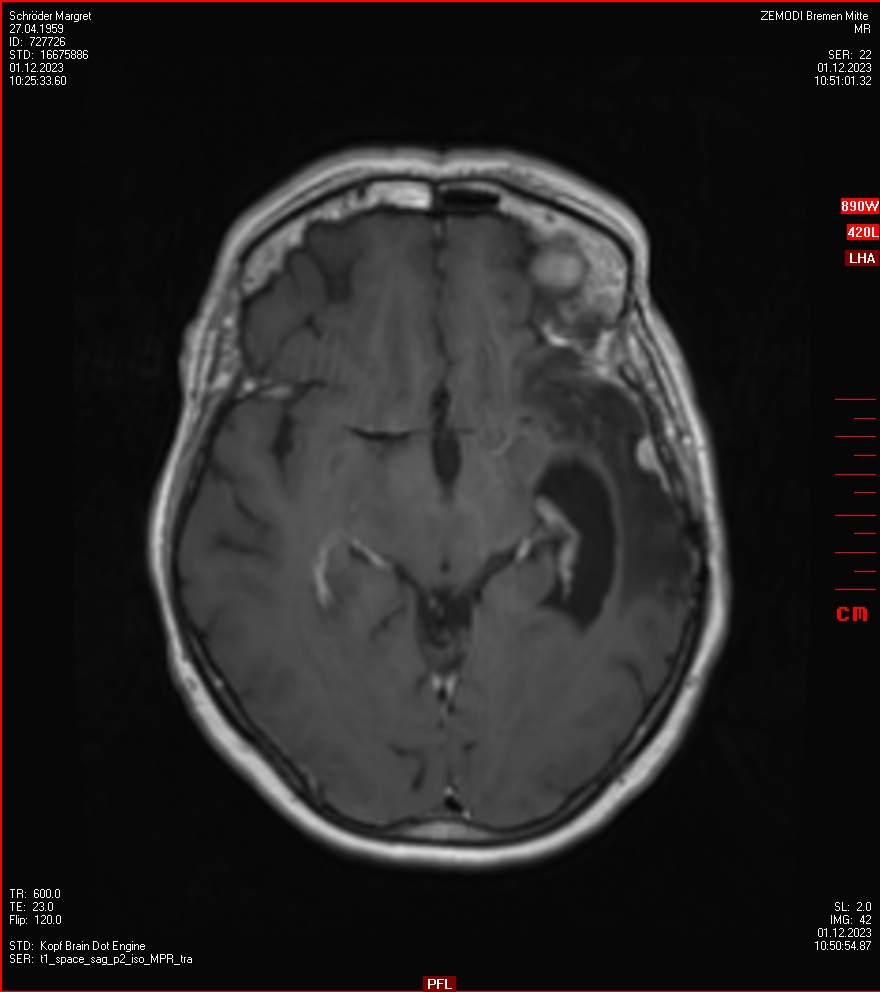

Zum Vergleich nun auch die Bilder vom 1.12.2023:

Ich denke, in den letzen 12 Monaten sind da ein paar Rezidive gewachsen,  vor 12 Monaten waren sie auch schon zu erkennen - vorher noch nicht. Nun hoffe ich auf den Rat des Spezialisten. Hoffendlich kann man etwas machen.